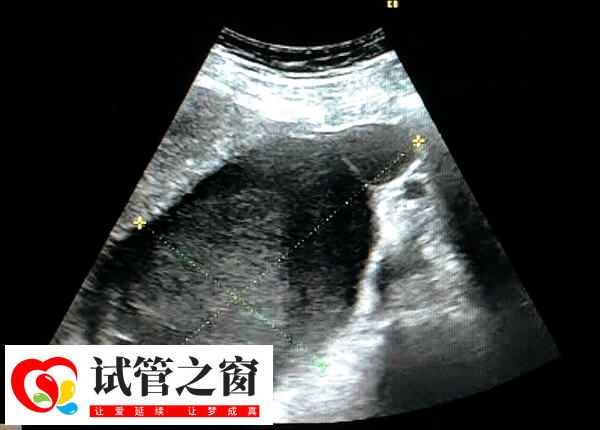

5、子宮出血

試管嬰兒移植后,女性可能會(huì)出現(xiàn)輕微的子宮出血。這是因?yàn)榕咛ブ矔r(shí)會(huì)刺激子宮壁,導(dǎo)致輕微出血。然而如果子宮出血較多或持續(xù)時(shí)間過(guò)長(zhǎng),可能意味著試管嬰兒沒(méi)有成功。